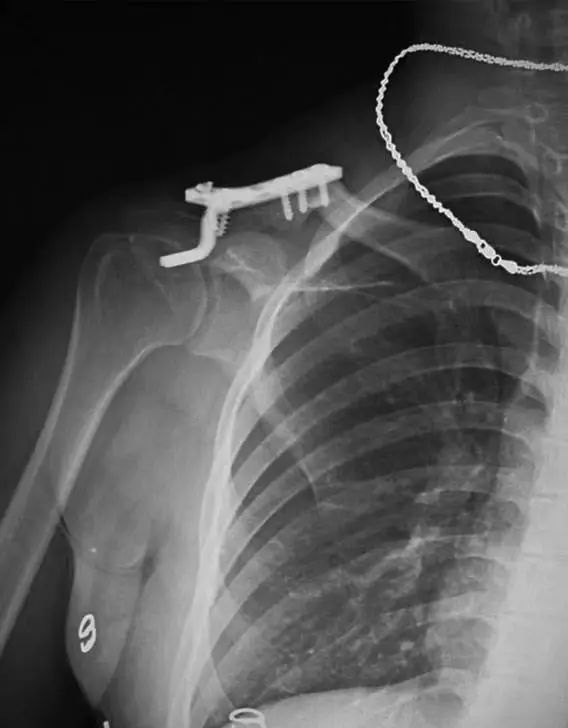

因此,我们目前所采取的方法为应用缝合锚钉(SuperRevo Anchor)加异体肌腱进行固定。手术采取60°沙滩椅位,经肩峰后角向喙突做Langer切口,切开三角肌~胸大肌筋膜显露骨折后对骨折进行复位,对断裂的喙锁韧带清创而不进行修补,以两枚缝合锚打入喙突基底,锁骨上钻孔后将缝合锚的尾线依次穿过骨孔后打结固定,为加强固定效果,加用异体肌腱绕过喙突基底并穿过锁骨孔后打结固定。术后颈腕吊带制动3周后开始肩关节功能锻炼。

锁骨板有哪些【每周科普】锁骨骨折分中段、外段、内段,治疗方式也有差异_https://www.jmylbn.com_新闻资讯_第14张

我们用此方法治疗了近百例患者,目前未发现出现固定失效的情况,术后随访结果显示肩关节功能大多获得了良好的恢复。